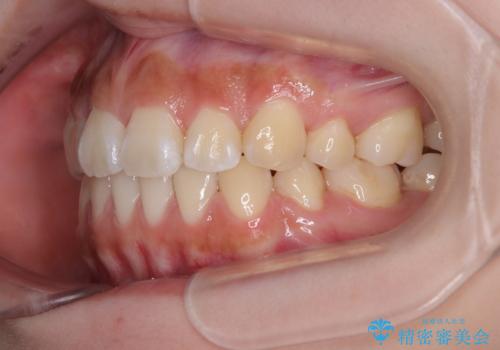

口元の印象が劇的に解消され、気にしていたガミースマイルも図らずも改善することができました。

- 口元から飛び出てしまう前歯を気にして来院された患者様です。

上下前歯が嘴のように前方に突出しており、唇が閉じにくい状態であったため、上下左右の第一小臼歯4本を抜歯して、口元の突出感を改善することとしました。